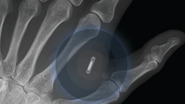

Ce face microcipul pe care George Buhnici și l-a implantat în mână[Sursa foto: Facebook: Georghe Buhnici]

Buhnici a povestit pe blogul său, buhnici.ro, despre beneficiile pe care le aduce „pilula-minune”. De fapt, nu este vorba despre un singur cip, ci despre o capsulă din sticlă cu trei cipuri, cu tehnologii diferite, care iau locul cartelelor magnetice și cipurilor NFC, identice cu cele folosite la plata „contactless” (fără contact) cu telefonul.

„Spuneam că e de dimensiunea unui bob de grâu și îți poți cumpăra unul de pe internet. Nu fac reclamă acestei firme, dar există momentan puțini furnizori de implantabile. Acesta vine într-un plic și apoi îl poți implanta la un dermatolog, chirurg, o asistentă medicală sau chiar un specialist în tatuaje. Sau nu trebuie să o faci deloc. Nu câștigi și nu pierzi nimic”, a scris Buhnici la câteva luni după ce și-a luat noua „jucărie”.